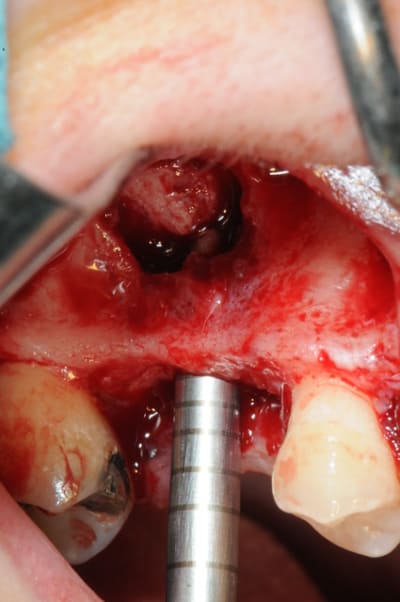

Petite question lors de l'application du VitalOs : As tu d'abord appliqué du VitaOs dans la partie palatine du sinus avant de placer ton implant où juste injecter le Vitalos une fois l'implant mis en place ?

l'application type du VitalOs, avec le bone splitting.

le protocole tel qu'il est d'écrit voudrait que l'on applique d'abord une couche de vital os en palatin - laisser durcir - mettre l'implant puis mettre une dernière couche.

ici, j'ai mis l'implant- maintenu la membrane de Schneider en poussant avec l'embout sur celle ci et terminer l'injection du produit. c'est l'un des avantages de ce produit, il est livré avec deux embouts donc les deux solutions sont possibles pour une même seringue.